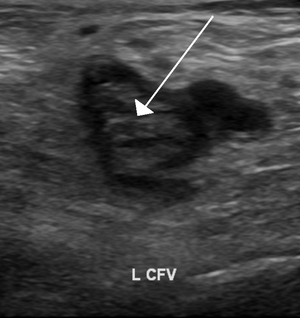

Individuals suspected of having DVT may be assessed using a clinical prediction rule such as the Wells score. A D-dimer test may also be used to assist with excluding the diagnosis (because of its high sensitivity) or to signal a need for further testing. Diagnosis is most commonly done with ultrasound of the suspected veins.

DVT diagnosis requires the use of imaging devices such as ultrasound. Clinical assessments, which predict DVT likelihood, can help determine if a D-dimer test is useful. In those not highly likely to have DVT, a normal D-dimer result[lower-alpha 7] can rule out a diagnosis.

Imaging

Imaging tests of the veins are used in the diagnosis of DVT, most commonly either proximal compression ultrasound or whole-leg ultrasound. Each technique has drawbacks: a single proximal scan may miss a distal DVT, while whole-leg scanning can lead to distal DVT overtreatment.[3] Doppler ultrasound,[58] CT scan venography, MRI venography, or MRI of the thrombus are also possibilities.[3][56]